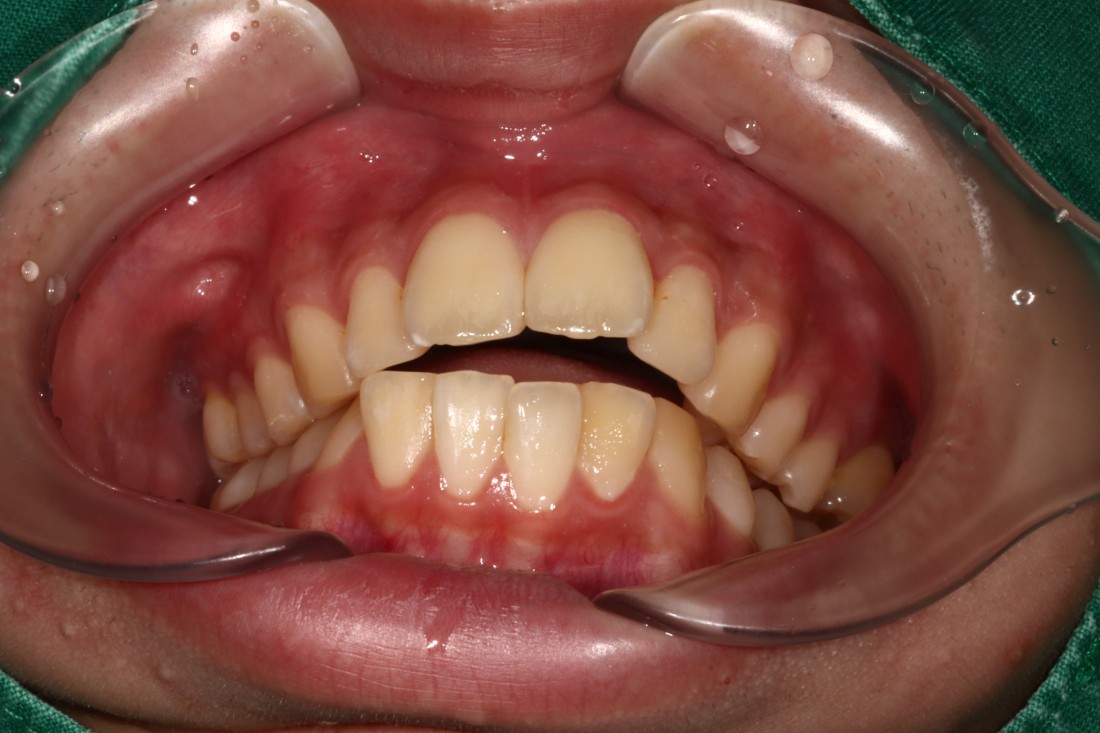

광주 개방교합 교정을 위해

방문해주신 30대 남성 환자분의

교정 전 사진입니다.

어금니를 맞닿게 하여서 입을 다물어도

윗니와 아랫니가 만나지 않는데요.

정상적인 교합은 윗니가 아래치아를

살짝 덮으면서 앞니로도 음식을

잘 씹어먹을 수 있게 되어있지만,

이렇게 개방교합의 경우에는

윗니와 아랫니가 만나지 않기 때문에

앞니로 부드러운 면발을 씹는 것 조차

불가능한 경우가 많습니다.